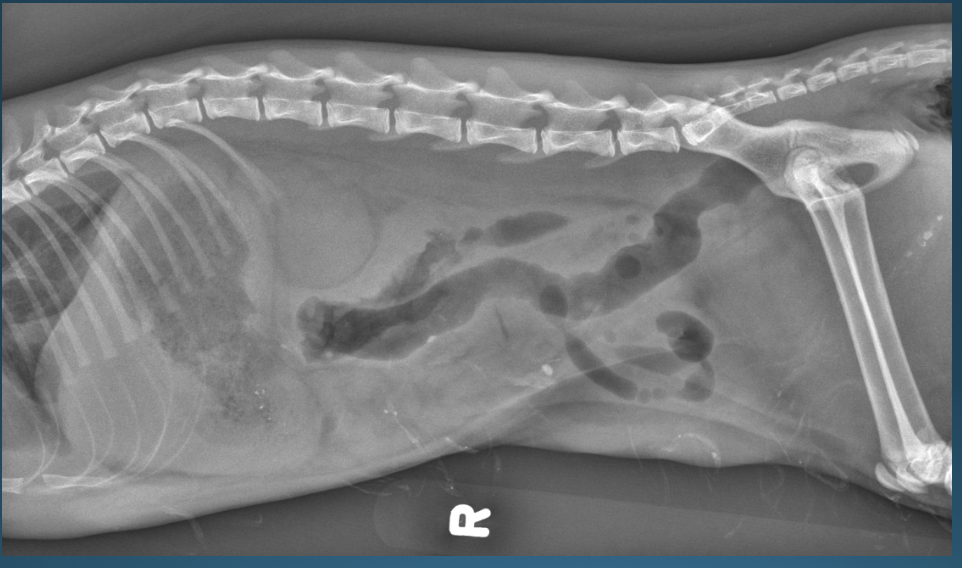

What is shown in these images?

normal abdomen and normal body wall in a dog